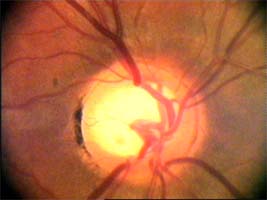

Jaké informace nám mohou říci cévy o poškození terče glaukomem? Cévy kopírují povrch terče, jeho nerovnosti se projevují záhyby cév. Při glaukomu mohou být obnaženy cévy, které dříve probíhaly v n. lemu. Při pokročilého glaukomu se zužují arterie a vzniká arteriovenózní nepoměr!

Na dolním pólu terče je patrný zálom vény, která zviditelňuje přítomnost i hloubku exkavace až k dolnímu okraji terče.

V nasálním horním kvadrantu terče vidíme obnažené cévy, které dříve probíhaly v lemu. Toto obnažení může být jedním z prvních příznaků glaukomové neuropathie.

(tenze 40-50 torr) Na obrázcích vidíme terče levého oka pacientky, u které se ani opakovanými operacemi nepodařilo snížit nitrooční tlak.

Kromě zvětšení a vertikálního protažení exkavace je zřetelné zúžení arterií, zatímco vény jsou zúženy jen méně zřetelně.